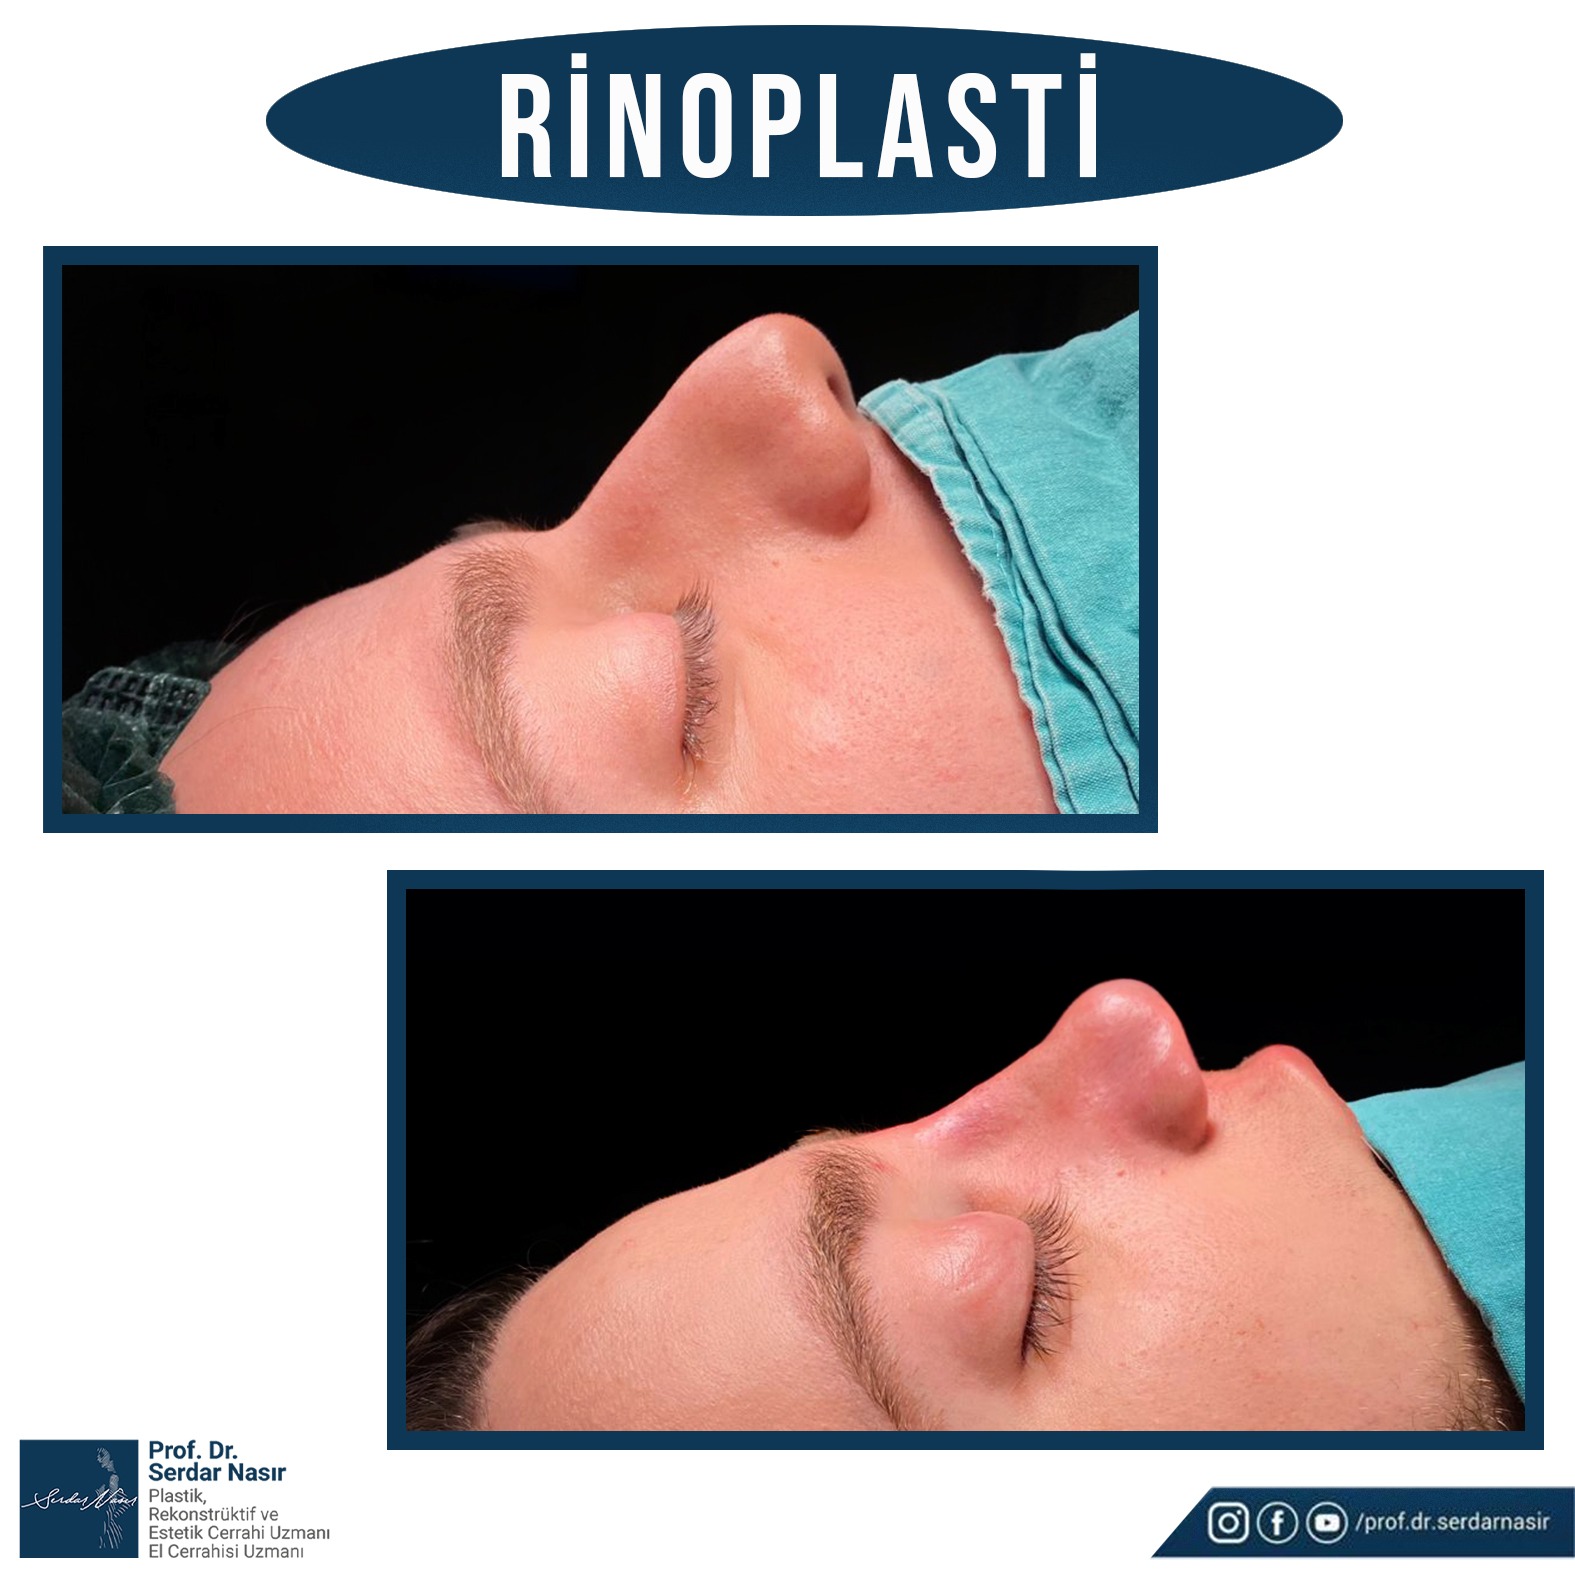

Estetik burun ameliyatı bana göre plastik cerrahinin en zor ameliyatlarından biridir. Çünkü burunda estetik olarak güzel bir sonuç elde etmeye çalışırken aynı zamanda fonksiyonel sonuçta yani hastanın nefes alıp vermesininde bozulmaması ve hatta sorun varsa düzeltilmesi gereklidir. Bu nedenle oldukça dikkatli yapılması gereken ameliyatlardır. Şu da bir gerçektir ki en çok revizyon dediğimiz ilk ameliyattan sonra tekrar bazı küçük deformitelerin veya hoşa gitmen bazı ayrıntıların düzeltilmesinin yapıldığı ikinci ve bazen üçüncü ameliyatlar en çok bu grupta saptanmaktadır. Bu nedenle özellikle ilk ameliyatın başarılı şekilde yapılması bu revizyon olasılığını azaltacaktır. Yine de estetik burun ameliyatı olmayı planlayan bir kişi her zaman için bir revizyon olasılığını akılda tutmasını öneririm.

Kişisel tecrübeme gelince ameliyat sonrası şişliklerin daha az olması, dokuları daha az travmatize etmesi gibi düşüncelerle ilk planda kapalı tekniği tercih etmekteyim. Ancak hastanın burun deformitesi özellikle burun ucuna yönelik ağırlıktaysa veya çok detaylı bir cerrahi girişim yapılacaksa açık tekniği tercih etmekteyim. Ancak tecrübelerime göre kapalı teknik ile açık tekniğe gerek kalmadan bir çok hastanın sorunu çözülebilmektedir.

Septumdeviasyonu ve ona ikincil teşkil edebilecek konka büyümesi nefes alma sorununun başta gelen nedenlerindendir. Bu bozukluğun düzeltilmesi zaman zaman estetik ameliyatlara eşlik eder zaman zaman ise hastalar sadece bu sorunla başvururlar. Eğer estetik ameliyatla birlikte yapılacaksa estetik kaygılar ön planda tutularak septum ve konka cerrahisinin ikinci plana alınması nefes zorluklarına ameliyat sonrasında da devam etmesine ol açabilir. Sadece bu sorunla gelmiş hastada ise zaman zaman bu cerrahi sonrası burunda bazı estetik sorunlar oluşabilir. Bu nedenle estetik ve fonksiyonel harmoninin hastalarda çok iyi sağlanması gereklidir.